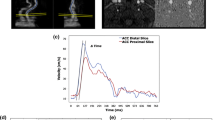

hfCIMT (a) and ufPWV (b) significantly greater in people with T1D versus healthy controls. Data represented as box-and-whisker plots. Control healthy controls, T1D people with type 1 diabetes, CIMT carotid intima-media thickness, PWV pulse wave velocity, PWV-SF systolic foot PWV, PWV-DN dicrotic notch PWV. * denotes p < 0.01

ufPWV higher in type 1 diabetes

Pulse wave velocity at both the systolic foot (PWV-SF) and dicrotic notch (PWV-DN) was significantly increased in T1D (PWV-SF = 5.29 ± 0.23 m/s vs 5.50 ± 0.37 m/s, p < 0.01; PWV-DN = 7.54 ± 0.46 m/s vs 7.92 ± 0.41 m/s, p < 0.01) (Fig. 2b). After controlling for age, sex, and BMI, T1D had a 0.267 m/s increase in PWV-SF and 0.432 m/s increase in PWV-DN (Table 2). This corresponds to a relative percent change between T1D and controls of 5.0% and 5.7% for PWV-SF and PWV-DN, respectively. On within-group analysis of control and T1D groups, both PWV-SF and PWV-DN showed no correlation to sex, BMI, A1c, T1D duration, total cholesterol, SBP, or DBP (data not shown). PWV-SF was correlated with age (Pearson correlation coefficient r = 0.39, p = 0.01) and LDL (r = 0.38, p = 0.02) in T1D but not in controls. PWV-DN was negatively associated with LDL (r = − 0.45, p = 0.03) in controls, but had no association in T1D.